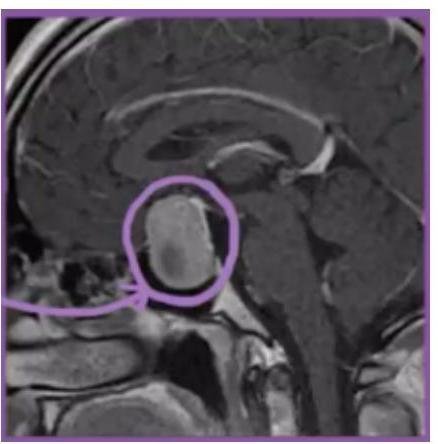

# ACROMEGALIA / GIGANTISMO: DEFINICIÓN Afección por la que la **hipófisis** elabora demasiada **hormona del crecimiento** después de haber terminado el crecimiento normal del esqueleto. Esto hace que los huesos de las manos, los pies, la cabeza y la cara crezcan más de lo normal. La causa de la acromegalia puede ser un tumor en la hipófisis. Si el exceso de GH surge antes del cierre de las epífisis se denomina: **GIGANTISMO**. ## ETIOLOGÍA **ADENOMAS HIPOFISIARIOS** perfectamente definidos (95%) - 75% son macroadenomas. - Los niveles de GH se relacionan directamente con el tamaño del tumor. ## Growth Hormone (GH) HYPOTHALAMUS SECRETES **GH-RELEASING HORMONE** EVERY COUPLE HOURS CAN INCREASE WITH: - LOW **BLOOD GLUCOSE LEVELS** - LACK OF FOOD - INCREASED EXERCISE - INCREASED SLEEP  DIRECT EFFECTS: TISSUES WHERE GH STIMULATES **CELLULAR METABOLISM** - ORGAN GROWTH  # CLÍNICA - **CRECIMIENTO ACRAL** - Enfermedad crónica debilitante - Cambios maxilofaciales - Crecimiento exagerado de los huesos y partes blandas - Crecimiento de manos, pies y perímetro craneal - Prognatismo - **CEFALEA** (40%) - Desarrollo exagerado de la lengua (**MACROGLOSIA**) - Rasgos faciales toscos. - **HIPERHIDROSIS** **RESISTENCIA INSULINA** (80%), **INTOLERANCIA GLUCOSA** (50%), Diabetes Mellitus Incremento riesgo **Ca Colon, Tiroides**  Hipertrofia laríngea - Voz cavernosa # DIAGNÓSTICO ## NO se deben medir los niveles aleatorios de GH **IRM CON PRESENCIA DE ADENOMA**  **DETERMINACIÓN DE LOS NIVELES DE IGF-I + SUPRESIÓN DE LA SECRECIÓN DE GH TRAS SOBRECARGA DE GLUCOSA** a. CRITERIOS i. Presencia de GH elevado 2 horas después de sobrecarga oral con glucosa. ii. Niveles elevados de IGF-1 para el sexo y edad del paciente. ## TRATAMIENTO ## CIRUGÍA TRANSESFENOIDAL - Indicado en micro y macroadenomas. ## RADIOTERAPIA - Pacientes no curados tras cirugía. ## ANÁLOGOS DE SOMATOSTATINA - Riesgo quirúrgico, rechazo de cirugía, macroadenoma no resecado.